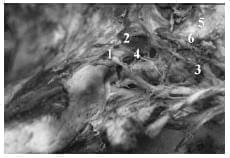

4. Triángulos de la pared lateral del seno cavernoso derecho.

1-III par. Indicado T. Superior

2-IV par.

3-T.Parkinson.

4-V1

5-T.Antero lateral.

6-V2.

7-T. extremo lateral.

8-V3

9-T.Glassock.